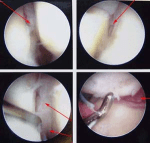

ארתרוסקופיה של שורש כף היד הינה כלי נהדר. ניתן להשתמש בה לכאב כרוני, כאשר האבחנה אינה חד משמעית – אבחנה ארתרוסקופית. ניתן להשתמש בה גם לטיפול במקרים אחרים רבים שאחרת ידרשו חתכים פתוחים גדולים יותר, כגון כריתת סינוביטיס (ניקוי של דלקת), תיקון רצועות (בייחוד הרצועה בצד האצבע הקטנה של שורש כף היד, ה-TFCC),

ואף לטיפול במספר שברים בשורש כף היד.

מאחר והחתכים הם קטנים נגרם פחות כאב מאשר בניתוח פתוח גדול יותר, וההחלמה תהיה לרוב פחות כואבת ויותר מהירה. בנוסף, האתרוסקופ מאפשר גישה עמוקה לשורש כף היד ולמעשה לכל אזורי שורש כך היד וכך חתך קטן מאפשר בחינה מקרוב ויסודיות.